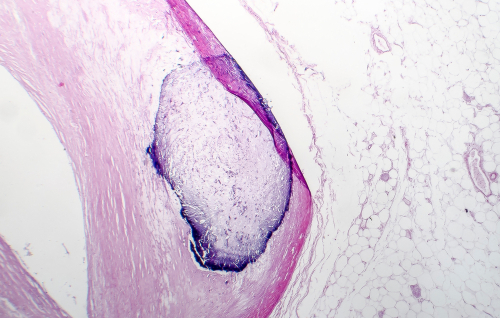

Coronary artery calcification (CAC) is the buildup of calcium in the arteries which can cause blood vessels to narrow and lead to the development of heart disease. Early signs of CAC, in which calcium specks appear in artery walls, can be detected through a computed tomography (CT) scan.